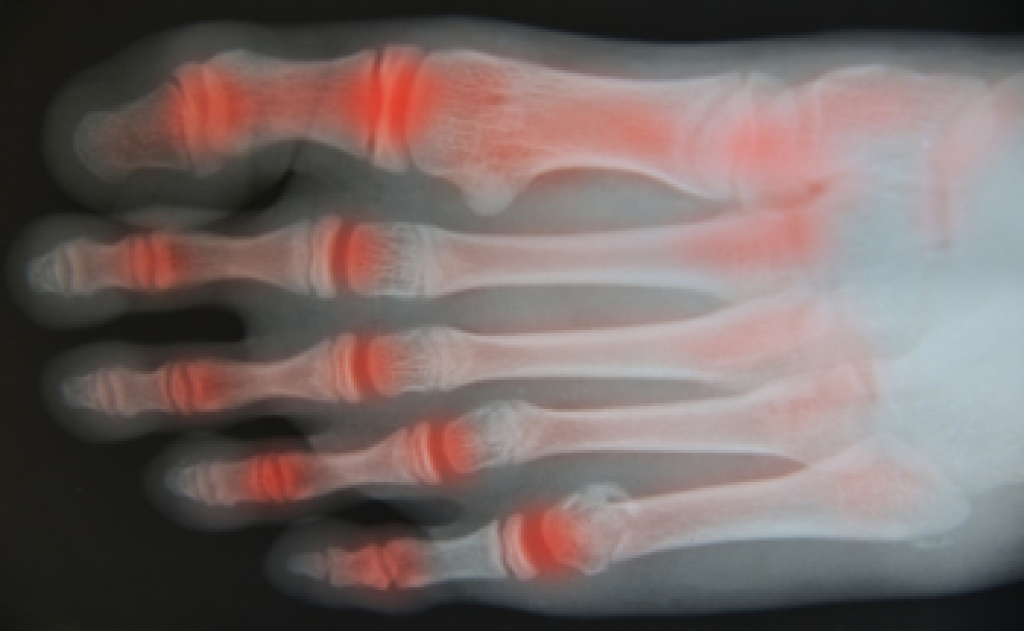

Arthritis Can Affect the Feet and Ankles

Arthritis, a chronic inflammatory condition, manifests its influence on the human body in various ways, and the feet and ankles often bear a significant brunt of its impact. The joints in these lower extremities, intricate in structure and essential for mobility, become vulnerable targets. Inflammatory arthritis types, such as rheumatoid arthritis, can result in painful swelling, stiffness, and joint deformities, limiting the range of motion. Osteoarthritis, characterized by the gradual breakdown of cartilage, leads to pain and reduced flexibility in the affected joints. The feet, comprising numerous small joints, are particularly susceptible, and the gradual progression of arthritis can affect the arches, toes, and ankle joints. As these joints endure wear and tear, daily activities can become increasingly challenging. Understanding the toll arthritis can take on the feet and ankles emphasizes the importance of early diagnosis, tailored treatments, and proactive measures. If you have arthritis and your feet and ankles are affected, it is strongly suggested that you consult a podiatrist who can help you to manage this condition.

Arthritic Foot Care

Arthritis is a term that is commonly used to describe joint pain. The condition itself can occur to anyone of any age, race, or gender, and there are over 100 types of it. Nevertheless, arthritis is more commonly found in women compared to men, and it is also more prevalent in those who are overweight. The causes of arthritis vary depending on which type of arthritis you have. Osteoarthritis for example, is often caused by injury, while rheumatoid arthritis is caused by a misdirected immune system.

Arthritic symptoms range in severity, and they may come and go. Some symptoms stay the same for several years but could potentially get worse with time. Severe cases of arthritis can prevent its sufferers from performing daily activities and make walking difficult.

If you suspect your arthritis is affecting your feet, it is crucial that you see a podiatrist immediately. Your doctor will be able to address your specific case and help you decide which treatment method is best for you.